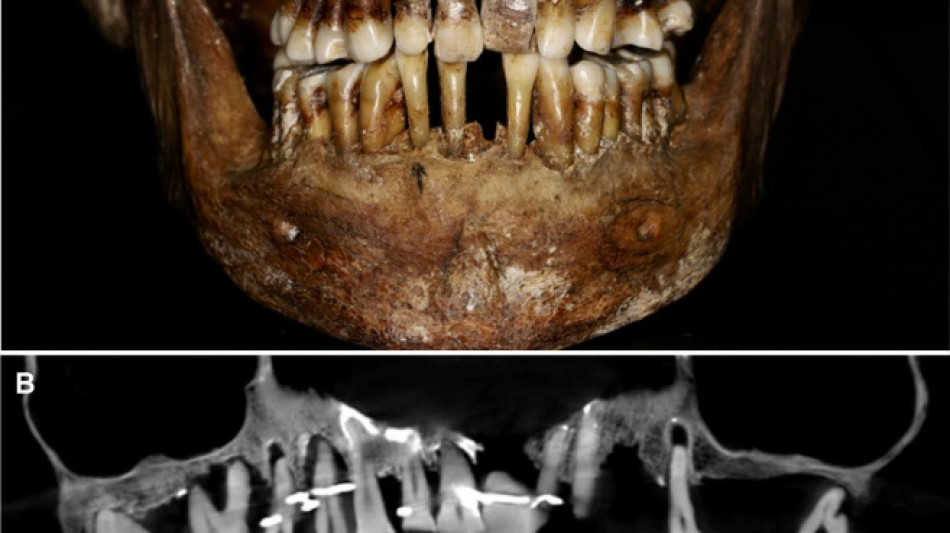

French aristocrat's golden dental secret revealed 400 years on / Photo: Handout - INRAP/Rozenn Colleter/AFP/File

Embalmed in a lead coffin, her skeleton -- and teeth -- were remarkably well preserved.

At the time the archaeologists noticed that she had a dental prosthetic, but they did not have advanced scanning tools to find out more.

Thirty-five years later, a team of archaeologists and dentists have identified that d'Alegre suffered from periodontal disease that was loosening her teeth, according to a study published in the Journal of Archaeological Science: Reports this week.

A "Cone Beam" scan, which uses X-rays to build three-dimensional images, showed that gold wire had been used to hold together and tighten several of her teeth.

She also had an artificial tooth made of ivory from an elephant -- not hippopotamus, which was popular at the time.

But this ornate dental work only "made the situation worse", said Rozenn Colleter, an archaeologist at the French National Institute for Preventive Archaeological Research and lead author of the study.

The gold wires would have needed repeated tightening over the years, further destabilising the neighbouring teeth, the researchers said.